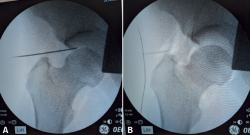

Figura 8. A: introducción de la aguja guía desde el portal anterolateral, asegurando que el bisel está orientado hacia la cabeza femoral; B: delimitación del contorno capsular radiotransparente mediante la insuflación de aire dentro de la articulación para comprobar que nos encontramos dentro de la articulación.

Realizaremos el portal artroscópico AL bajo control escópico para confirmar el posicionamiento de la aguja guía. Introduciremos la aguja guía con el bisel mirando hacia la cabeza femoral, para evitar dañar el cartílago de este. Visualizaremos la ubicación de la articulación coxofemoral para intentar triangular el punto de entrada, de manera que accedamos por la parte más lateral del acetábulo; para ello, podemos imaginar una línea que esté a mitad de camino entre el pubis y la ASIS. Como norma general, orientaremos la aguja guía unos 20° en dirección cefálica. Si hemos corregido adecuadamente la anteversión femoral del paciente con la rotación interna de la pierna, como se explicó anteriormente, deberíamos poder entrar con una dirección paralela al suelo. Por tacto, detectaremos la resistencia inicial de la fascia lata y, en segunda instancia, la resistencia de la cápsula articular, identificando la entrada dentro de la articulación. Comprobamos con el tacto mediante alambre de nitinol (con extremos romos) la ubicación intraarticular, mediante tacto con el fondo acetabular y mediante control de radioscopia. Insuflamos 30 cc aire para realizar una aeroscopia, que nos ayuda a identificar el reborde del rodete acetabular e identificar la comunicación fisiológica con el psoas, importante para prevenir una posible extravasación abdominal de suero (Figura 8). Para minimizar el riesgo de una entrada translabral, se recomienda valorar la retirada de la aguja guía tras la insuflación de aire y volver a entrar asegurando evitar la huella del rodete acetabular (Tabla 4).